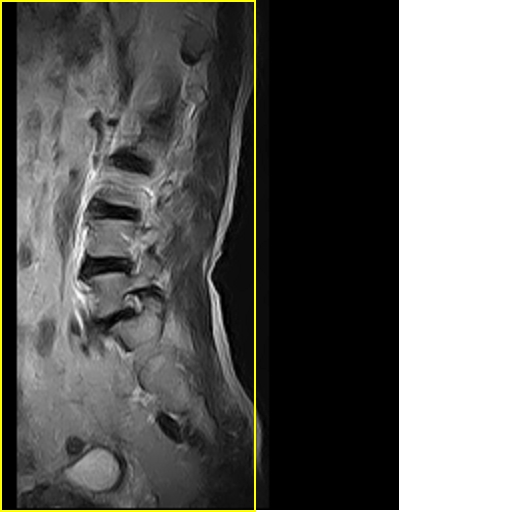

男,78岁,右下肢跛行两月.

退行性骨关节病:增生、椎间盘变性、膨出...

退行性病变:增生、椎间盘变性、膨出[l4-5、l5-s1 椎间盘膨出]

退行性骨关节病:增生、椎间盘变性、膨出..黄韧带肥厚.

黄韧带肥厚.